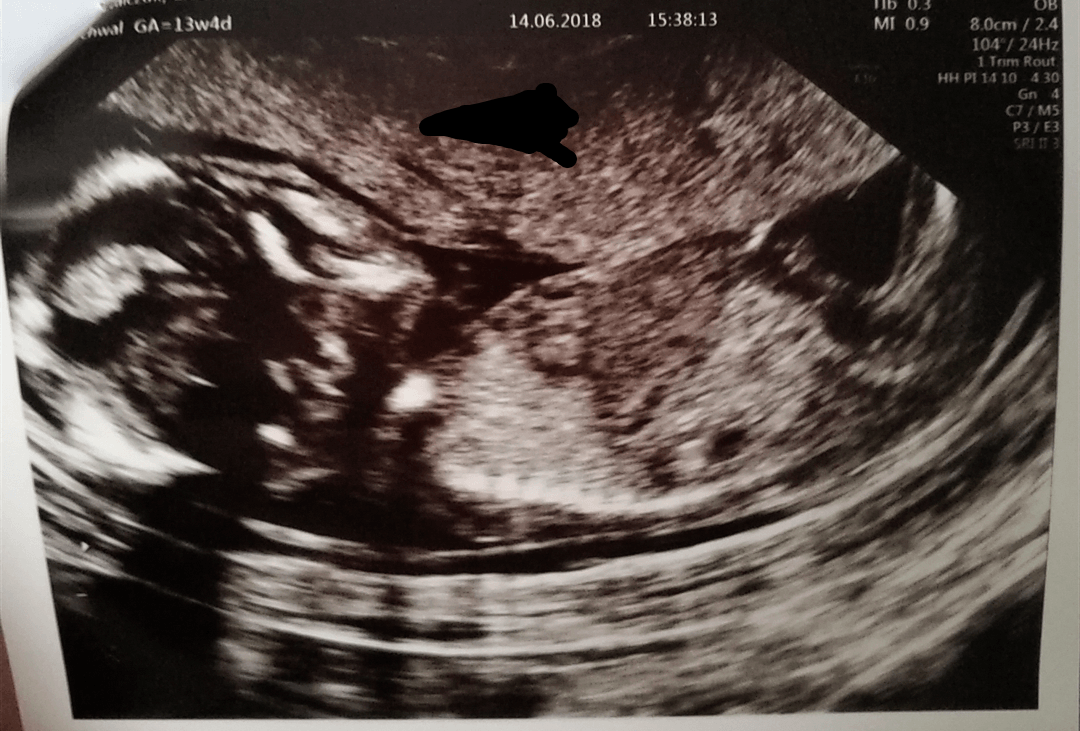

Hej. Dziś byliśmy na prenatalnych. Lekarz powiedział że wszystko jest ok, przy okazji stwierdził na 99% dziewczynkę. Pamiętam post mamy ginekolog o płci i zgodnie z tym maleństwo wygladało nam na chłopca. Co myślicie?? Wiadomo nie podważam kompetencji lekarza ale liczyliśmy z mężem na chłopca mój mówi że jest jeszcze 1% szans że się zmieni.

Hej. Dziś byliśmy na prenatalnych. Lekarz powiedział że wszystko jest ok, przy okazji stwierdził na 99% dziewczynkę. Pamiętam post mamy ginekolog o płci i zgodnie z tym maleństwo wygladało nam na chłopca. Co myślicie?? Wiadomo nie podważam kompetencji lekarza ale liczyliśmy z mężem na chłopca mój mówi że jest jeszcze 1% szans że się zmieni. Zobacz załącznik 867351